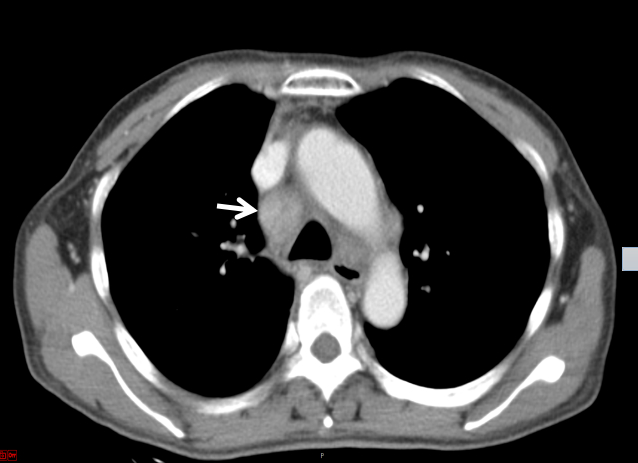

后再因“反复发热、多关节痛7月、皮疹3月”于2019-09-17入住本院风湿科。入院当天体温36.5℃,心率106次/min,呼吸20次/min,血压118/75 mmHg。步态正常,自主体位。左颈部肿大淋巴结。四肢和背部可见紫癜样皮疹,按压部分褪色,伴抓痕。腹软,肝脾未及。图 2为2019-09-21胸部CT结果,箭头所指为肿大淋巴结。

| 图 2 胸部CT示纵膈淋巴结改变 |